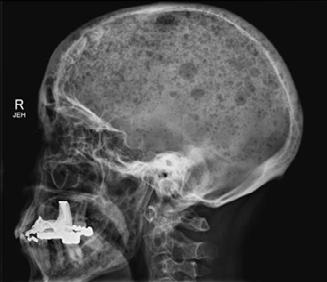

Ból kostny, jeden z najczęstszych objawów szpiczaka plazmocytowego, występuje u około 2/3 w momencie rozpoznania i niemal u wszystkich chorych w przebiegu choroby. Obrazowanie medyczne pozwalające na dokładne określenie obecności, liczby i lokalizacji zmian ogniskowych kośćca jest niezbędnym elementem wstępnego postępowania diagnostycznego oraz oceny stopnia zaawansowania choroby, jako że zmiany osteolityczne, jako jeden z elementów uszkodzenia narządowego oraz zmiany pozakostne będące biomarkerem nowotworu, definiują aktywną chorobę i stanowią wskazanie do niezwłocznego rozpoczęcia terapii.

Choć konwencjonalne badanie radiologiczne stosowane jest od wielu lat i nadal pozostaje ważnym elementem podstawowej przesiewowej diagnostyki, charakteryzuje się ono wieloma istotnymi ograniczeniami. Podstawowe wady tej techniki to: niska czułość detekcji zmian osteolitycznych, trudności w ocenie niektórych obszarów kośćca (miednica, kręgosłup), brak możliwości rozróżnienia złamań kręgów wtórnych

do osteoporozy od złamań patologicznych w przebiegu szpiczaka, a także brak możliwości przeprowadzenia dokładnej oceny odpowiedzi na leczenie, ze względu na zbyt niską czułość techniki względem procesu gojenia kości. Wobec wymogów diagnostycznych narzucanych przez nowe kryteria rozpoznania szpiczaka plazmocytowego konwencjonalna radiologia jest niewystarczająca (tab. 4.1.).

Ryc. 4.1. RTG czaszki – liczne ogniska osteolityczne.